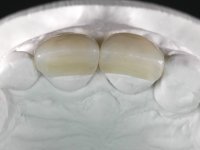

• Reabitação dos dentes Incisivos Centrais Superiores com facetas de cerâmica feldspática.

O tratamento iniciou-se com a re -preparação do coto do espigão falso coto fundido, com o objetivo de colocar as linhas de acabamento cervical com uma localização intra-sulcular e simultaneamente confecionar uma coroa provisória adaptada. Com um tratamento ortodôntico muito simples, fechou-se o diastema entre os incisivos centrais superiores e estabilizou-se esta posição com um arame colocado na superfície palatina dos centrais, funcionando como contenção. Posteriormente procurou-se fazer uma tração ortodôntica lenta do dente 2.2 com o intuito de diminuir, ainda que muito ligeiramente a perda óssea vertical nessa zona. Finalizada a tração, foi feita a extração do dente 2.2 e a zona foi reabilitada provisoriamente com uma coroa de resina composta colada aos dentes adjacentes. Foi colocado um implante dentário na zona do dente 2.2 sendo novamente colada a coroa provisória em resina, reabilitando provisoriamente a paciente durante o período de osseointegração. No dente 1.3 foi feita uma gengivectomia com bisturi elétrico, com a intenção de subir o nível cervical do 1.3 conseguindo uma maior harmonia com o dente 2.3. Estabilizados os tecidos moles, foi feita uma impressão com a técnica de moldeira aberta, utilizando silicones de adição de consistência “putty” e “light”. A recolha da cor, tanto da componente dentária como dos tecidos moles foi feita pelo ceramista no consultório.  No laboratório as impressões foram passadas a gesso e deram origem a modelos de trabalho que foram devidamente analisados. Foi decidido confecionar um “abutment” metalo-cerâmico aparafusado sobre o implante. Este “abutment” foi fundido com uma liga nobre e posteriormente revestido a cerâmica coronária e gengival. Dada a inclinação do implante o aparafusamento condicionou de forma inevitável a saída do orifício do parafuso pela superfície vestibular. No sentido de esconder esta situação, o desenho do “abutment” já foi idealizado com a intenção de acomodar na superfície vestibular a colagem de uma faceta feldspática. Este “abutment” foi provado em boca e foram feitos ajustes no componente cerâmico gengival. A sua adaptação aos tecidos moles foi feita tanto de forma subtrativa, com broca, como de forma aditiva, acrescentando resina composta de tonalidade gengival. Este acrescento de resina seria orientador do ceramista na colocação final da cerâmica de tonalidade gengival. A coroa que reabilitaria o dente 1.3 foi cimentada nesta consulta de prova com cimento de ionómero de vidro reforçado com resina composta. Finalizado o trabalho em laboratório da faceta sobre o 1.2 e o “abutment” e a faceta para o implante este foi colado em boca, após a colocação do isolamento absoluto. O trabalho satisfez plenamente a paciente. Durante oito anos a paciente foi seguida regularmente, mostrando-se agradada com o tratamento efetuado, no entanto começou a mostrar interesse em intervir esteticamente nos incisivos centrais superiores. Decidida a segunda fase da nossa intervenção, foi feita a preparação dentária dos dentes 1.1 e 2.1 para a colocação de duas facetas feldspáticas. Particular cuidado foi tido na preparação inter-proximal distal junto ao “abutment” do implante. Foi preciso avaliar muito pormenorizadamente o eixo de inserção da faceta em relação ao “abutment”. As facetas feldspáticas foram confecionadas em laboratório e posteriormente coladas em boca após a colocação de isolamento absoluto. Um ano após, iniciamos a nossa terceira fase de tratamento, após a faceta colada no dente 2.1 ter fraturado. A preparação dentária foi feita sobre a faceta colada, procurando estender mais para palatino o interface inter-proximal distal. O objetivo seria passar para mais palatino do ponto de contacto o interface faceta-dente. O preparo dentário do dente 1.2 também foi muito reduzido, limitando-se a criar um eixo de inserção. Após confecionadas a coroa total e a faceta em laboratório foram coladas em boca. Primeiro foi colada a coroa utilizando-se um isolamento relativo com teflon, posteriormente foi colada a faceta após a colocação do isolamento absoluto. Na coroa utilizei este tipo de isolamento para evitar a utilização de grampos. Seria difícil de aplicar pela forma e dimensão do dente e agressivo para os tecidos moles. Após a colagem foi avaliada a integração oclusal do trabalho.